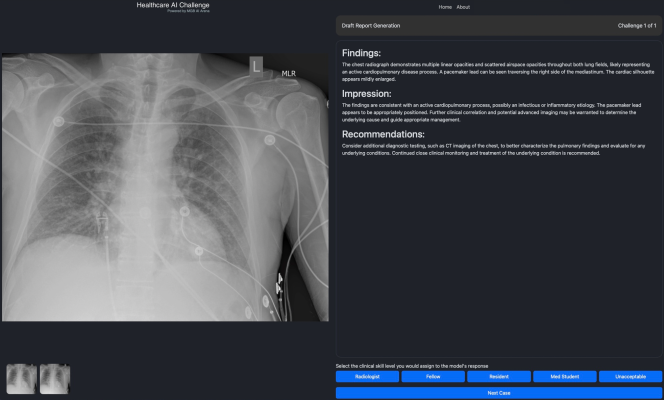

Participating healthcare professionals will be granted access to the Healthcare AI Challenge that features late breaking AI solutions they can assess for effectiveness on specific medical tasks, such as providing medical image interpretation, in a simulated environment. Participants with relevant healthcare credentials can then provide their feedback on the solutions’ performance and utility, which will generate publicly available insights and analytics. By crowdsourcing input from healthcare professionals, the Healthcare AI Challenge seeks to create continuous, consistent and reliable expert evaluations of AI solutions in medicine. Importantly, scaling the evaluation of these technologies and sharing the insights broadly and transparently can result in societal benefit for healthcare stakeholders and patients globally.

Health care professionals at instituyions that are a part of the Collaborative who register can log onto the Healthcare AI Challenge, select one of several events — such as image interpretation — and choose from a series of challenges to assess any one of the multiple foundation models available on the platform. The image interpretation challenges include questions focused on draft report generation, key findings, differential diagnosis, among others. The expert then rates the clinical skill level of the foundation models’ responses, which contributes to the insights and analytics rankings. Only verified healthcare professionals can participate in challenges that contribute to the rankings. The results of the Healthcare AI Challenge can be followed by the general public at HealthcareAIChallenge.org.